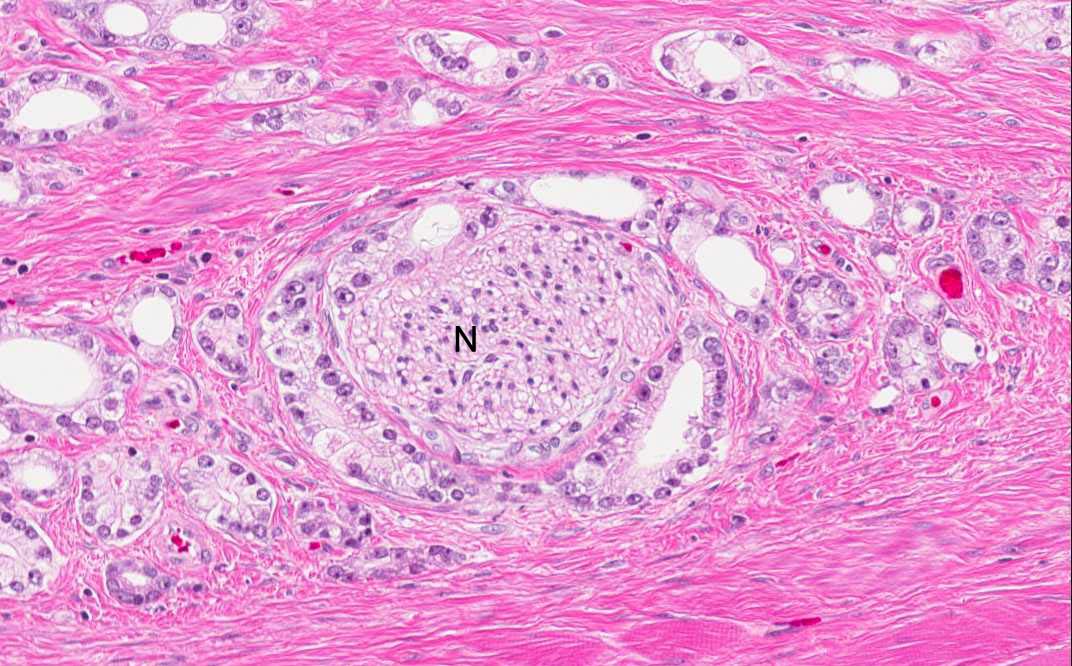

Area 4: Perineural invasion (invasion along the perineural space) is noted in this tumor. Note the peripheral nerve (N).

Hematoxylin & eosin

• Perineural invasion (spread of tumor along the perineural space) is common in prostatic adenocarcinoma and widespread in this particular tumor (Arear 3).